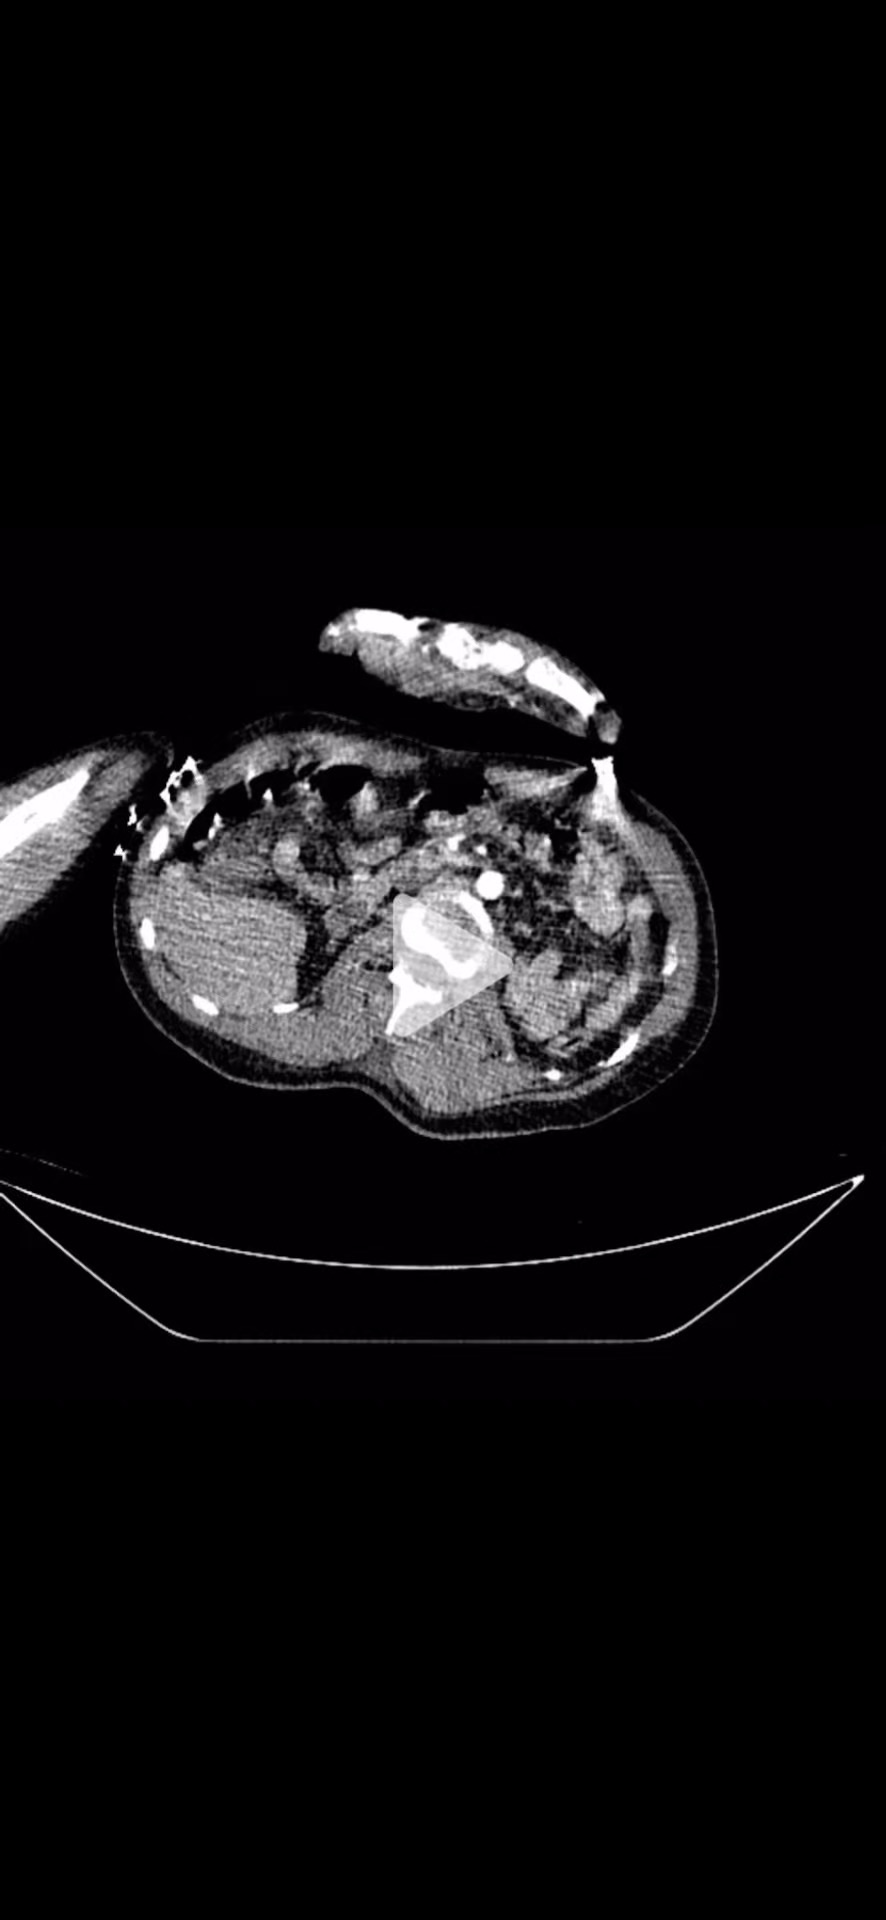

CTA动脉期: